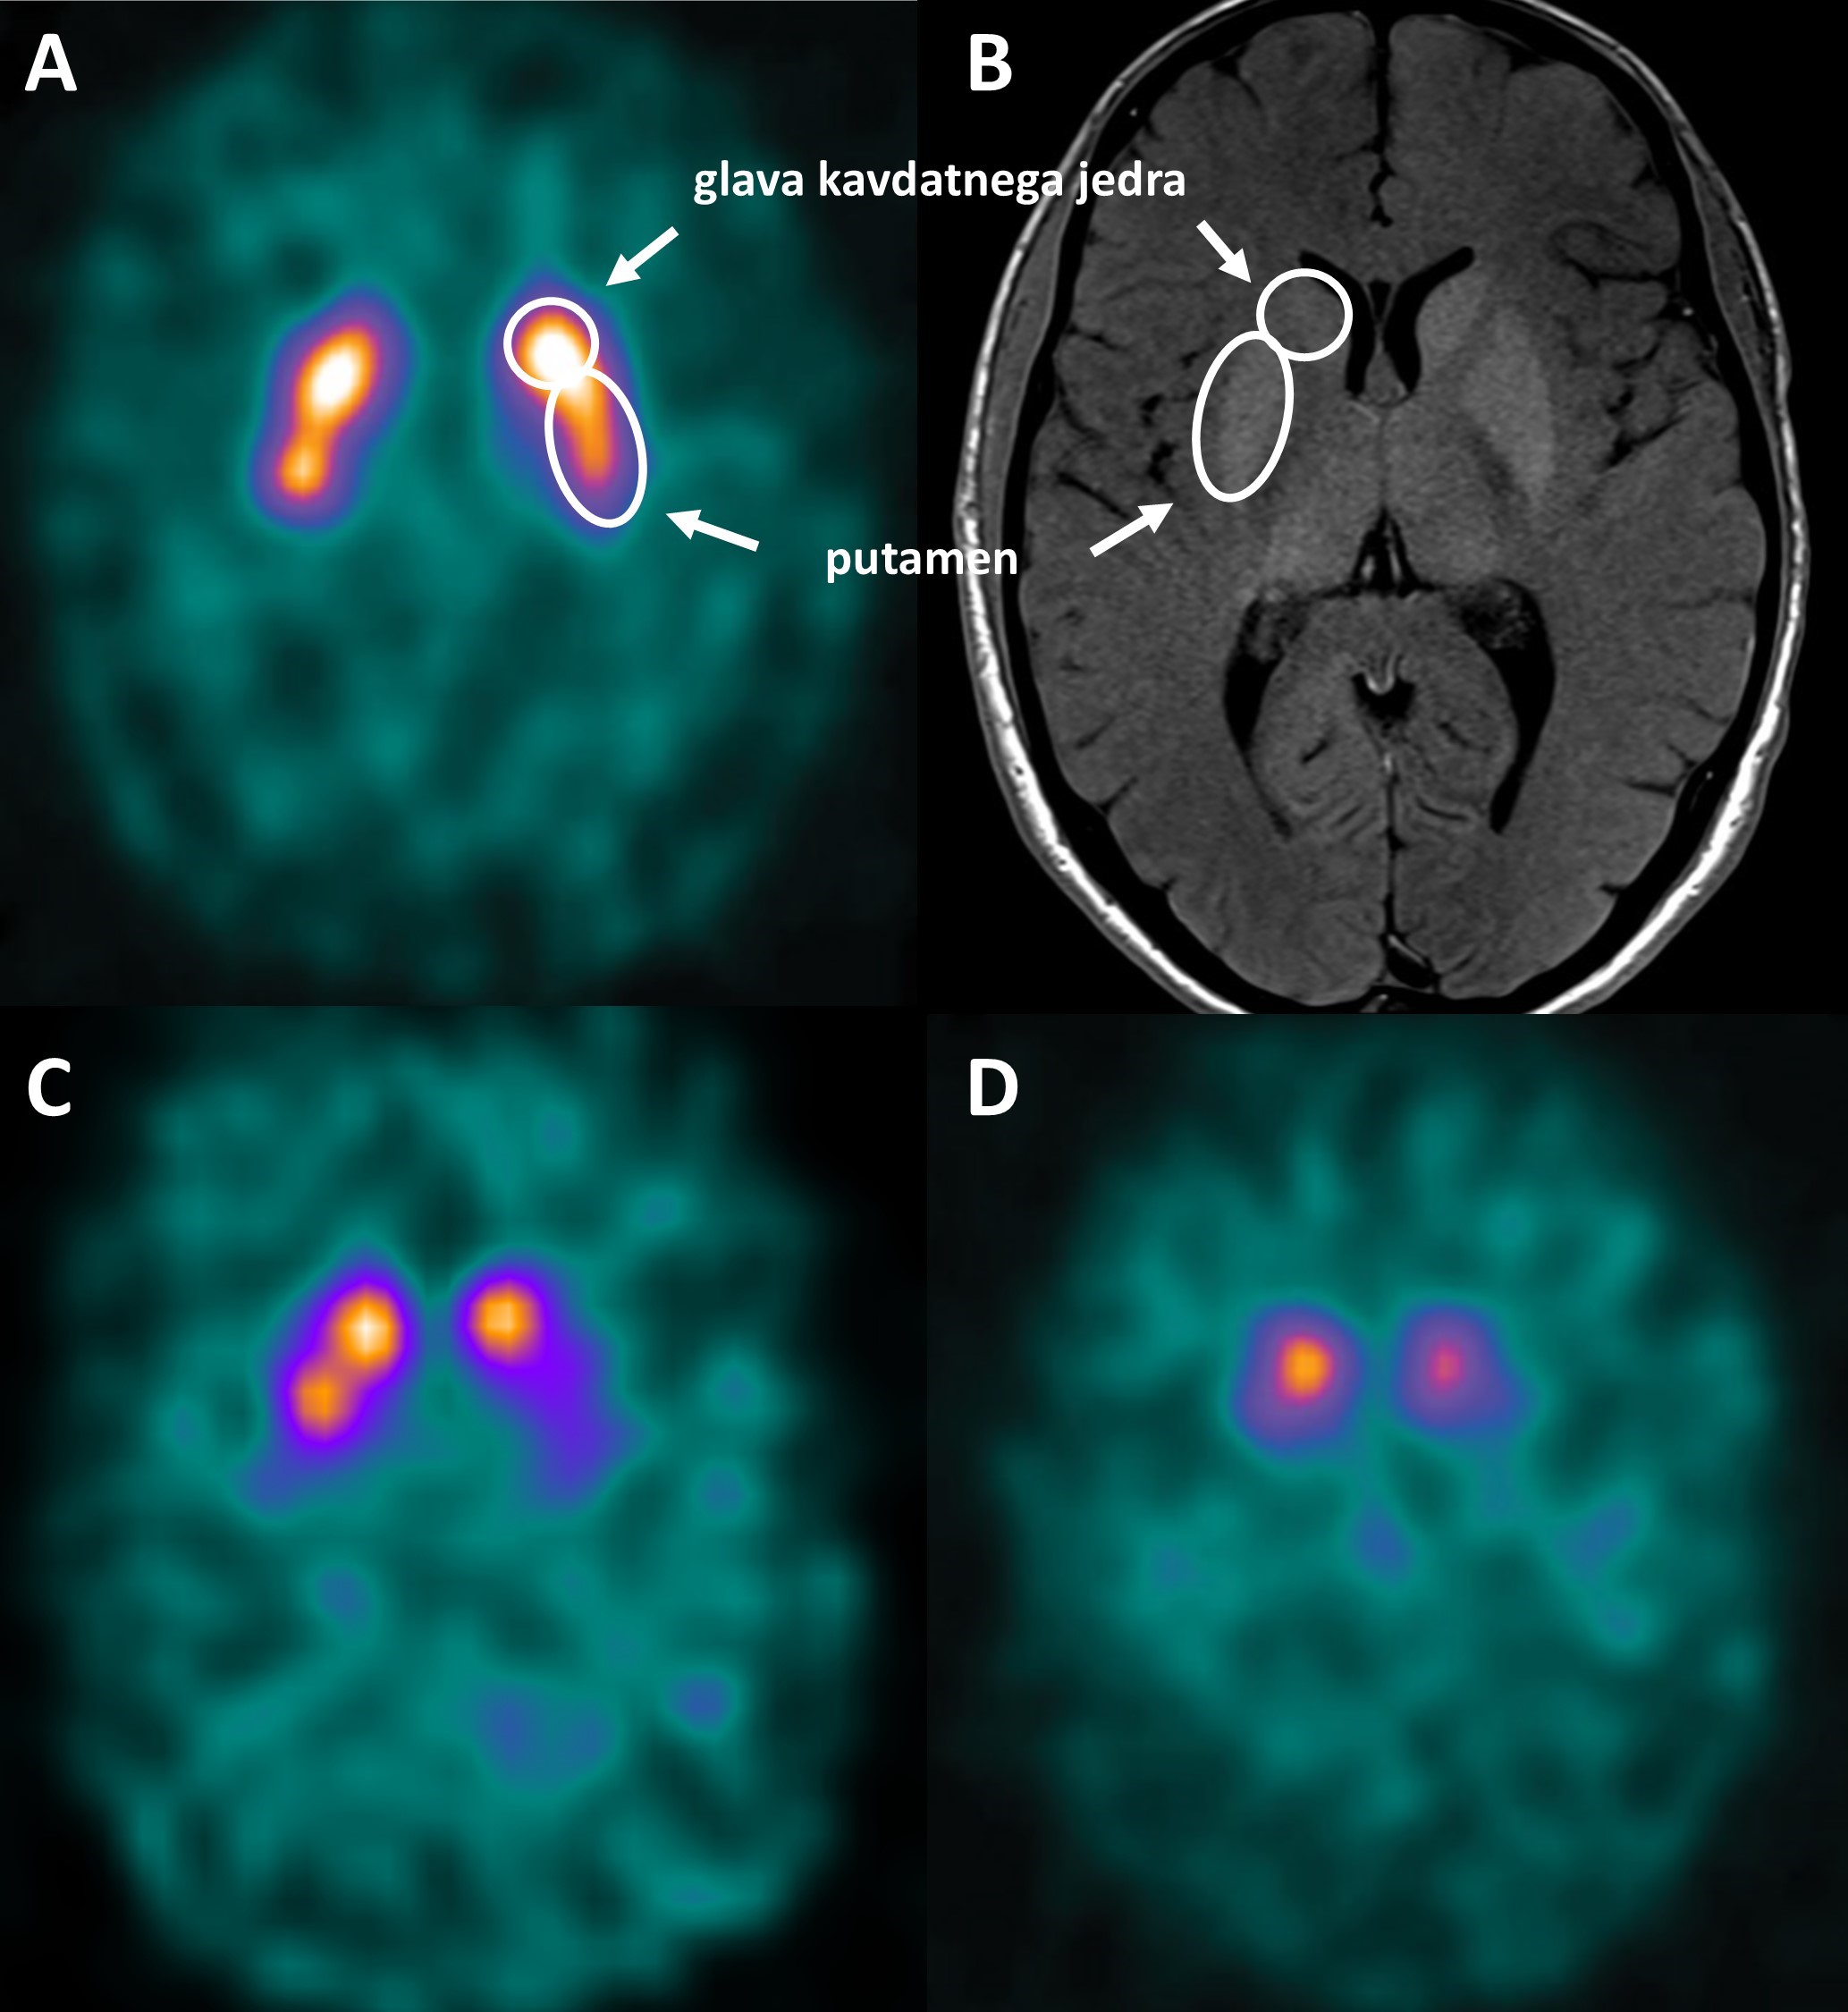

Dopaminergični sistem v bazalnih ganglijih sestavljata presinaptični del, ki ga tvorijo dopaminergični nevroni, projicirani iz črne substance v striatum, in postsinaptični del, ki ga predstavljajo striatalni nevroni. Presinaptični in postsinaptični nevroni se razlikujejo po svoji molekularni sestavi, kar izkoriščamo pri oceni integritete tega sistema z molekularnim slikanjem (Slika 1). Pri molekularnem slikanju uporabljamo radioaktivno označene molekule (radiofarmake), ki se vežejo na tarčne molekule v celici in oddajajo bodisi pozitrone bodisi gama žarke, ki jih zaznamo s kamerami PET (pozitronska emisijska tomografija) ali SPECT (ang. single photon emission computed tomography; enofotonska emisijska računalniška tomografija).

Okvara dopaminergičnih nevronov v črni substanci se pri PB začne pred prvimi znaki parkinsonizma. Ob postavitvi diagnoze je količina dopaminergičnih nevronov že zmanjšana za 50 odstotkov, v nadaljnjem poteku bolezni pa nevroni postopno linearno propadajo 5. Scintigrafija dopaminskega prenašalca z 123I-ioflupanom že v zgodnji PB razkrije zmanjšano kopičenje radiofarmaka, ki napreduje v kavdo-rostralni smeri (Slika 2). Sprva zaznavamo znižano kopičenje v posteriornih delih putamnov. Skladno s klinično sliko, je izpad kopičenja asimetričen, izrazitejši na strani kontralateralno od bolj prizadetih okončin (Slika 2C) 6. Sčasoma presinaptična dopaminergična okvara napreduje; kopičenje radiofarmaka je pri napredovali bolezni v putamnih odsotno, v kavdatnih jedrih pa izrazito in asimetrično znižano, vendar še zaznavno (Slika 2D) 5.

Scintigrafija dopaminskega prenašalca je patološka tudi pri atipičnih parkinsonizmih, kot sta multipla sistemska atrofija (MSA) in progresivna supranuklearna pareza (PSP), saj presinaptični nevroni propadajo tudi pri teh boleznih. Raziskave na večjem številu bolnikov so pokazale, da je razporeditev radiofarmaka pri teh boleznih drugačna: izpad ne sledi kavdorostralni smeri in je bolj simetričen 7 8. Na ravni posameznih bolnikov je tovrstna ocena razporeditve radiofarmaka premalo specifična za zanesljivo razlikovanje med različnimi nevrodegenerativnimi parkinsonizmi 7 8. Za razlikovanje med temi boleznimi lahko uporabimo radiofarmake, ki se vežejo na D2-receptorje (Slika 1); pri PB je ta vezava ohranjena, medtem ko je pri atipičnih parkinsonizmih znižana 9. Kljub temu je slikanje dopaminskih receptorjev trenutno omejeno predvsem na raziskovalno okolje. V rutinski diagnostiki za diferencialno diagnozo uporabljamo slikanje FDG-PET, ki se je izkazalo za bolj občutljivo in specifično 2 10 11 12. FDG-PET nam omogoča vpogled v regionalno možgansko presnovo, ki je tesno povezana z lokalno sinaptično aktivnostjo. Različne nevrodegenerativne bolezni prizadenejo specifične predele možganov in s tem povezana nevronska omrežja, kar se odraža v značilnih vzorcih kopičenja radiofarmaka, specifičnih za posamezne oblike nevrodegenerativnih parkinsonizmov 2 10 12.